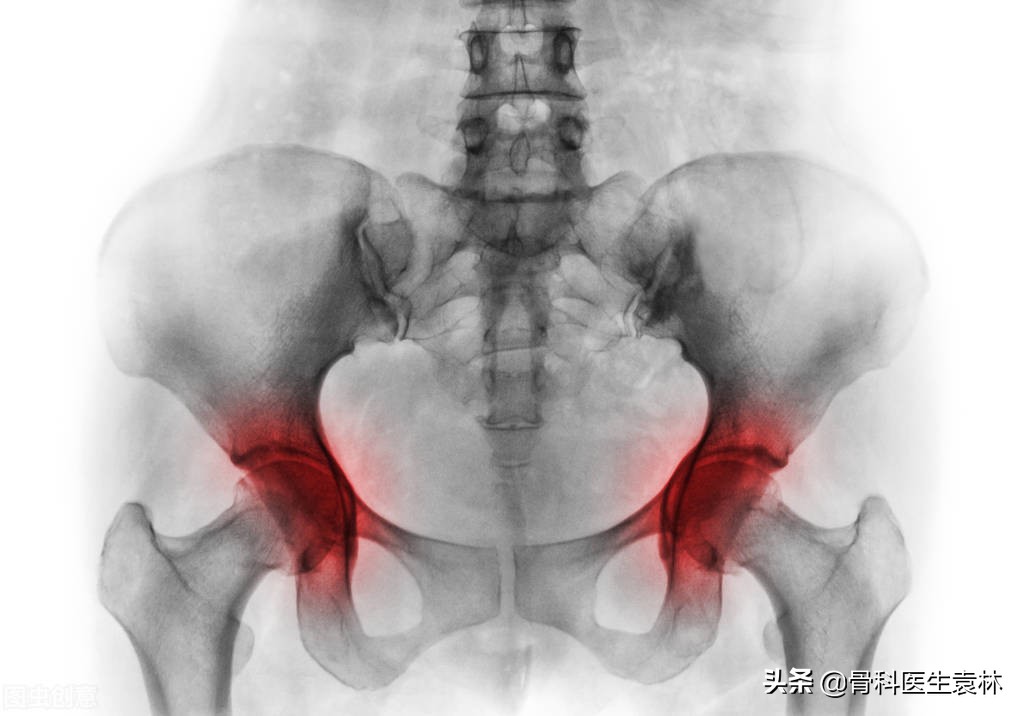

股骨头坏死又称股骨头缺血性坏死,系指股骨头血供受损或中断,导致骨髓成分结构改变及骨细胞死亡,而其后的自体修复导致股骨头结构改变,继而引起股骨头塌陷和功能障碍的疾病。

股骨头坏死早期症状中,患者的关节会显得比较的僵硬,髋关节屈伸不利,日常的活动也会受到一定的限制,患者出现下蹲困难、不能久站、行走鸭子步。早期症状为外展、外旋活动受限明显。

在早期症状中,之所以会出现跛行,这一般是由于髋痛、股骨头塌陷而导致的,一般情况是表现为进行性短缩性跛行,另外在晚期出现髋关节半脱位也会导致出现跛行,早期往往出现间歇性跛行,儿童患者则更为明显。